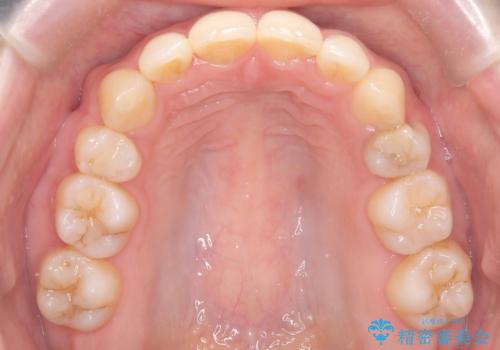

抜歯矯正により歯列のデコボコ(叢生)が改善し、前歯の突出も解消されたことで口元が下がり、すっきりとした印象となりました。

患者様にも大変ご満足いただけました。